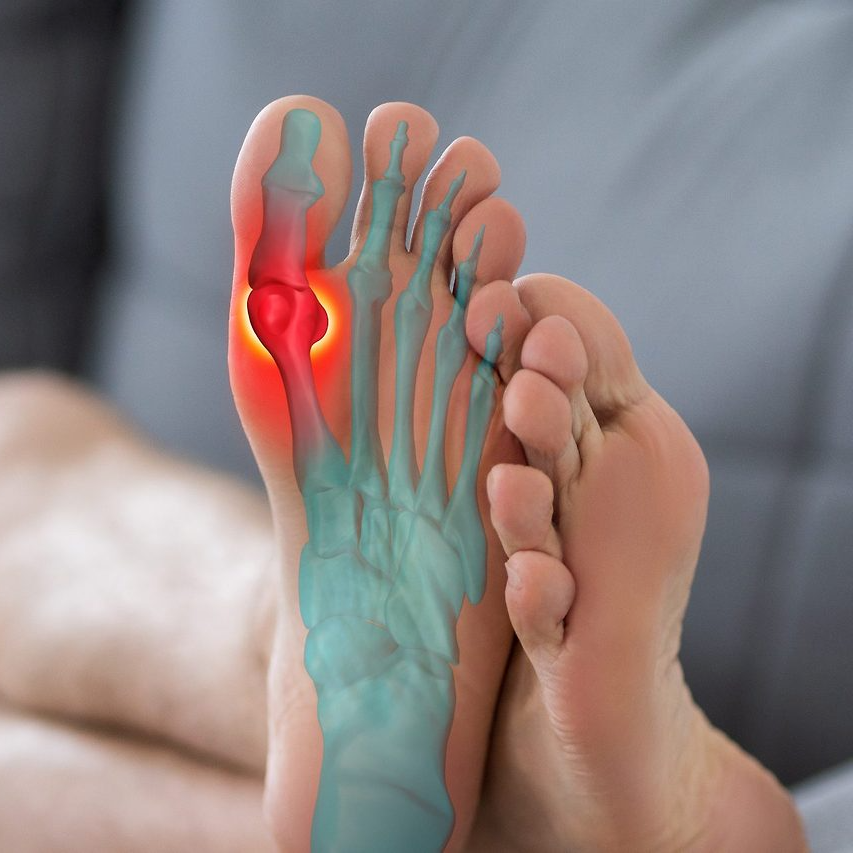

발가락 골절의 종류와 차이

발가락 골절은 손상 형태에 따라 몇 가지로 구분된다. 의료기관에서는 이를 영상검사로 확인한 뒤, 골절 유형에 따라 치료 및 위로금 지급액을 다르게 산정한다.

- 압박골절(압축골절)

외부 충격에 의해 뼈가 눌려서 납작하게 찌그러진 형태의 골절이다. 발가락보다는 주로 척추나 손가락 등에서 잘 발생하지만, 새끼발가락 끝부분이 강한 압력을 받을 경우 생길 수도 있다. 비교적 복잡한 골절로 간주되며, 뼈의 회복에 시간이 걸린다. - 폐쇄성골절

피부가 찢어지지 않고 뼈 안쪽에서만 골절이 일어난 경우로, 새끼발가락 골절 대부분이 여기에 속한다. 외부 출혈은 없지만 통증과 부종이 심하며, X-ray로 확인해야 진단이 가능하다. - 개방성골절

골절 부위가 피부를 뚫고 나와 피가 나는 형태다. 외부 감염 위험이 매우 높아 응급처치와 항생제 치료가 필요하며, 수술이 필수적이다. - 분쇄골절

뼈가 여러 조각으로 부서지는 형태다. 새끼발가락에서 이 경우는 드물지만, 큰 충격을 받은 교통사고나 낙상사고 시 발생할 수 있다.